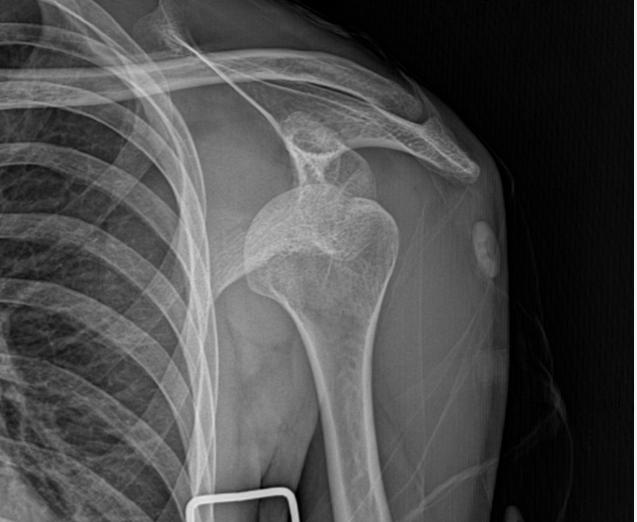

Shoulder Fracture

어깨골절

어깨골절은 상완골, 쇄골, 견갑골 등 어깨관절을 구성하는

뼈가 부러지는 것을 말합니다.

스포츠 활동 증가로 어깨골절 발생도 증가하고 있으며,

골다공증이 있는 경우에는 가벼운 충격에도

골절이 쉽게 발생할 수 있어 주의가 필요합니다.

어깨골절 수술이 필요한 경우

최소침습수술로 흉터 걱정없이 진행합니다

어깨골절은 골절 부위와 형태,

뼛조각의 어긋남 정도에 따라 수술 여부가 결정됩니다.

골절이 심하게 어긋났거나 관절면까지 침범한 경우에는

수술적 정복과 고정이 필요할 수 있습니다.